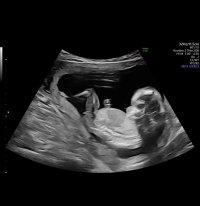

Åå, så kjedelig med dårlige bilder :/.. Jeg har dette også, men her ser man heller ikke stort. Jordmor sa ingenting om hva hun trodde eller noe som helst om kjønnet..Disse bildene var veldig dårlig til å være 14 uker. har du flere fra denne eller tidligere? burde være lett å se kjønn når man er så langt på vei. det på bilde nr 1 er ikke nub, det er en del av benet som har kommet med på bildet. Jeg tror det er jente da det ville vært veldig synlig i uke 14 om det var gutt. Ser og lang hvit strek på flere av bildene som samsvarer med jentenub.

? Er 13+1 her